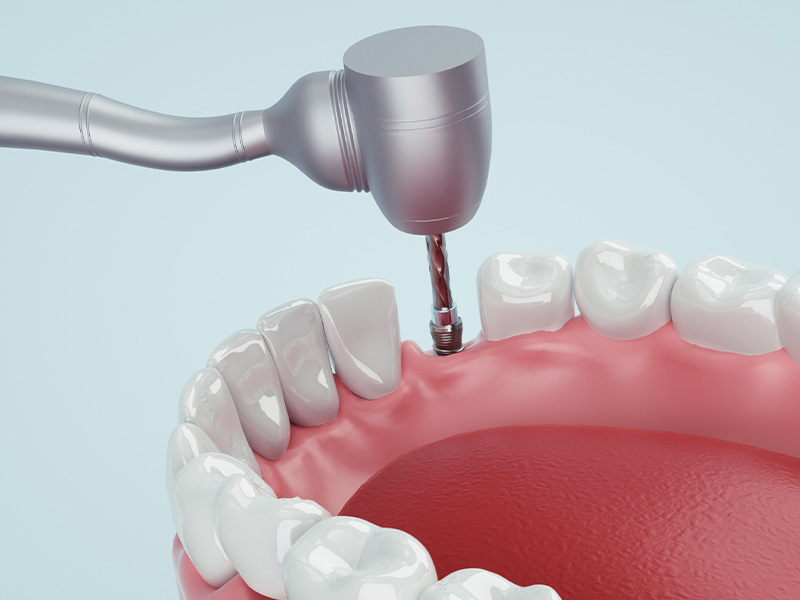

手術(インプラント埋入)

サージカルガイドを使用し、インプラント埋入1次手術を行います。。

インプラント埋入手術代 25万円(税込)~/1本

※手術内容により変動します。